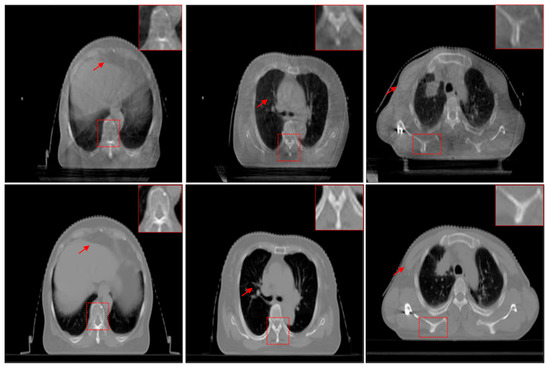

In this section, the registration results between the source CBCT and CT images and between the CBCT images enhanced using different enhanced algorithms and CT images are compared and analyzed. In this experiment, all the registration results are obtained by the same registration model [39]. In addition to visual analysis, we also give the SSIM values before and after the registration of these images to objectively measure the registration performance.

As shown in Figure 12, Figure 12a is the unregistered source CBCT and CT images. The SSIM value of the source images is 0.5532, and it can be seen from Figure 12a that the imaging position and size of the source CBCT and CT images are different. Figure 11b is the registration result by the source CBCT and CT, and the SSIM value is 0.7184 if the CBCT image is used directly for the registration task. In the enlarged image, the edge regions are not exactly aligned in Figure 12b. Except for the CBF enhancement method, the registration accuracy was improved after CBCT images were enhanced by other methods. For example, in Figure 12c, the SSIM value is 0.7486 by registering the MSR-enhanced CBCT and CT images, which shows improved accuracy of non-enhanced CBCT and CT registration. In other words, the enhancement of CBCT images is helpful to improve the registration accuracy of CBCT and CT, which is very critical and meaningful for IGRT.

Figure 12.

Registration comparison. The positions of the two images are shown in different colors. (a) Source CBCT and CT images. (b) Registration results of source CBCT and CT images. (c) Registration results of MSR-enhanced CBCT and CT. (d) Registration results of MSRCR-enhanced CBCT and CT. (e) Registration results of DCP-enhanced CBCT and CT. (f) Registration results of CBF-enhanced CBCT and CT. (g) Registration results of RRM-enhanced CBCT and CT. (h) Registration results of SMIPC-enhanced CBCT and CT. (i) Registration results of CBCT and CT enhanced by our method.

From the yellow arrows, it can be seen that our method’s results have the highest registration accuracy and achieve the best SSIM value of 0.7729. In the enlarged image, it can be seen that the proposed method outperforms the comparison methods in the registration accuracy of the edge regions. This is because the proposed method enhances the saliency features, which plays a key role in the registration process. In addition, since the proposed method includes the denoising step, the noise points on the edges of image that may affect the registration were filtered out, which also helps to improve the registration accuracy.